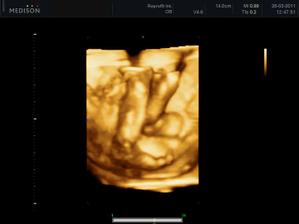

25.3.2011 - 3D utz - tak konečně víme, kdo nám to bydlí v bříšku - je to neuvěřitelný, ale je to malá princezna, hurááá hurááá je to holka - jsme moc šťastní - je to celej táta - i slza ukápla a tátovi taky.A kočenka s panem doktorem opět nespolupracovala, takže maminka opět chodila po chodbě jak trdlo, nakonec se umoudřila a přelehla si na druhej bok, nakonec se nám postavila na hlavu, asi jako už mě nechte být, no byla to sranda - krásný zážitek a nakupujeme růžovou 🙂 - měříme 24 cm a vážíme 320 g

31.5.2011 - Tak naše princezna nám dnešní 3D celý prospala a nehlo s ní vůbec nic, jelikož má už hlavičku hodně nízko v pánvi a ještě natočenou dovnitř, tak jsme neviděli obličejík, což nás moc mrzelo, ale jsme zdraví a hezky rosteme (1480g) a to je hlavní.

15.7.2011 - utz, malá váží 2630 g (37 tt), viděli jsme obličejík, celej táta a jsme v pořádku